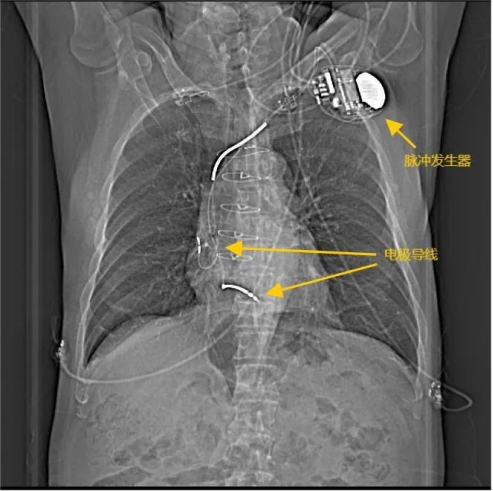

埋藏式心脏复律除颤器(ICD),ICD具有抗心动过缓、抗心动过速、低能电转复,以及高能电除颤等多种功能,是治疗危及生命的室性快速心律失常(心室颤动和室性心动过速)的一个多功能、多程控参数的电子装置,常被称为是装在身体里的“救命神器”。

这个“救命神器”有一个脉冲发生器埋藏在左侧锁骨下方皮肤里,还连接两根电极植入到心腔内,可以在王大爷再次出现室性心动过速甚至室颤时,迅速自动使脉冲发生器充电并发放电击能量(整个过程仅15秒左右),及时终止室速、室颤,挽救生命。